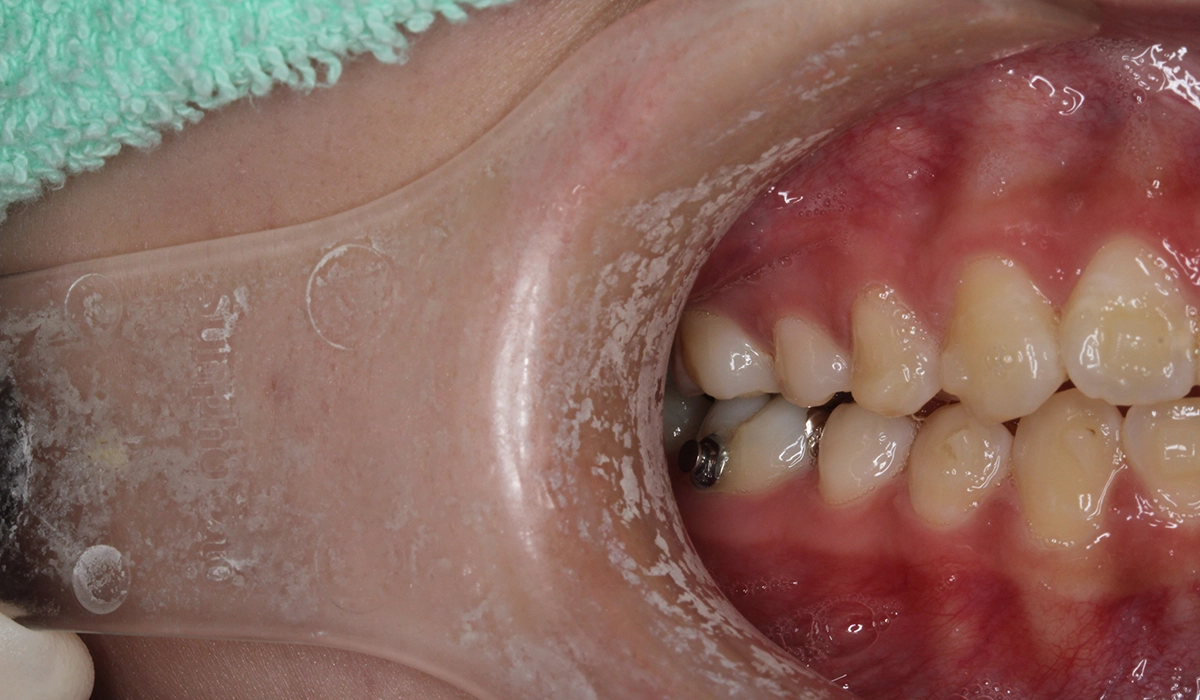

術前:左側

術後:左側